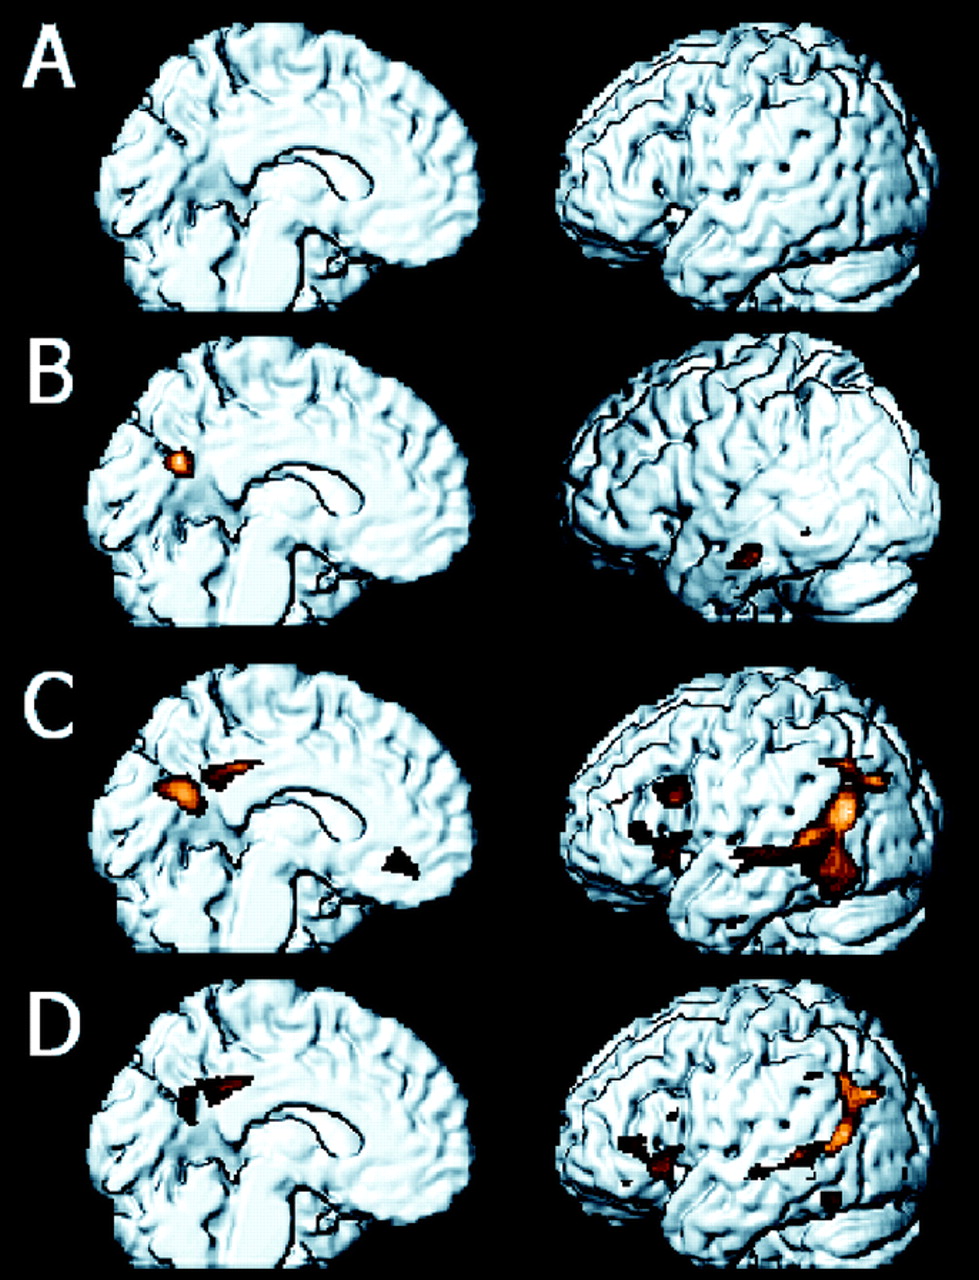

VBA没有显示海马组差异(图5)。符合其他VBA观察,广告显示患者减少MRglc双边后扣带(PCC)内,顶叶(IPC),颞(TC)和左额皮质(IFC)相比问以及MCI (p< 0.05,为多个比较)(见纠正图5和表e 1)。问和MCI之间没有VBA差异被发现。为探索的目的,通过之前的VBA MCI的研究,5、10、30 -我们删除了多重比较和校正审查数据少用保守概率阈值。MCI相对于问减少MRglc被发现的两个集群:左边中产TC和PCC(见左边图5和表e 1)。

图5。结果与SPM99分布分析。(一)没有MRglc健康老人之间的差异被发现(NL)和轻度认知障碍(MCI)p <0.05纠正为多个比较。(B)通过重置概率阈值的限制较少的价值p <0.001、未修正的两个集群MRglc减少被发现的左后扣带(PCC)(图左)和左颞上回(图右)MCI患者相比问。(C)宠物体素显示MRglc削减对阿尔茨海默病(AD)患者与本地语言相比,涉及颞顶、PCC和额叶皮质(p <0.05,为多个比较修正)。(D)宠物体素显示MRglc削减广告相比MCI患者,包括颞顶、PCC和额叶皮质(p <0.05,为多个比较修正)。这种减少区域分布类似于观察广告vs问但是更少空间扩展,表明皮质代谢减退也可能出现在一些MCI患者。领域的代谢减退(代表红黄颜色编码的规模)显示在内侧,外侧的观点volume-rendered空间归一化核磁共振图像。这些大脑区域对应于脑图谱坐标表e 1。